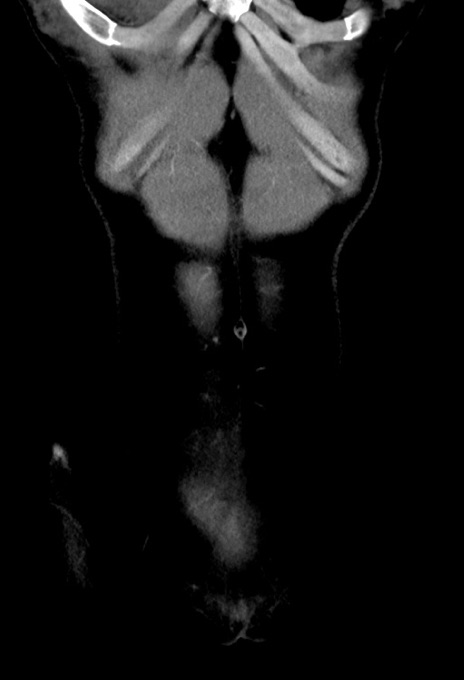

症例17(冠状断像)

【症例】20歳代女性

【主訴】嘔吐、下腹部痛

【現病歴】昨日夕食後に嘔吐し下腹部痛が出現。本日になっても嘔吐持続し改善しないため来院。

【身体所見】意識清明、BT 37.2℃、BP 108/67mmHg、腹部:平坦、やや硬、下腹部正中から右にかけて圧痛あり、反跳痛軽度あり、tapping pain(+)。

【データ】WBC 13600、CRP 14.94